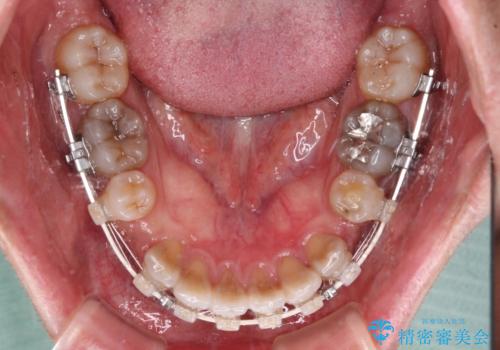

- 矯正装置

- 審美装置

- 飛び出した前歯を気にして来院された患者様です。

口元を引っ込めるために上下左右の第一小臼歯4本を抜歯することとしました。

速やかに治療を進めたいとのことで、表側のワイヤー装置で矯正治療を行うこととしました。